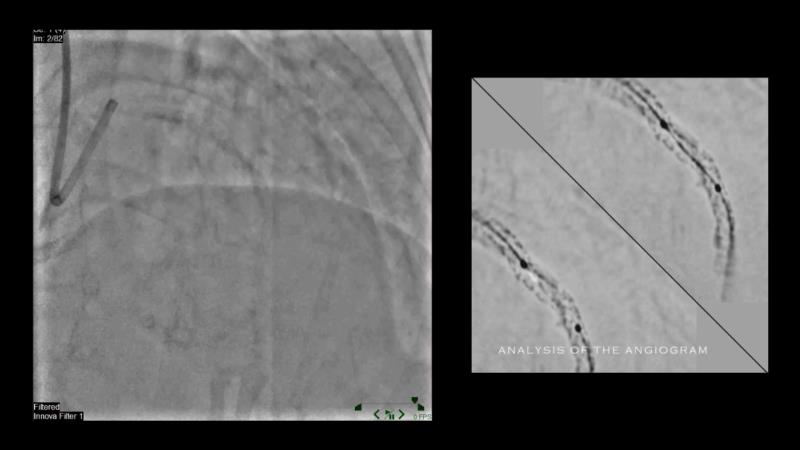

Discover the power of drug-coated balloon (DCB) technology in modern PCI. Understand the mechanism of action, including antiproliferative agents, drug transfer to the vessel wall, and effective inhibitory level and duration of vessel wall retention. Learn how IVUS can guide optimal lesion preparation, and explore the criteria for delivering effective DCB treatment.

- To learn how IVUS can guide optimal lesion preparation

- To learn the criteria for optimal lesion preparation prior to DCB application